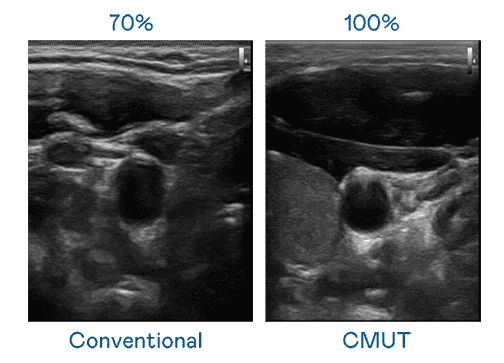

CMUT 技术是一种用电容式微机电元件来产生超音波讯号的技术。。。。与传统 PZT 压电式技术相比,,CMUT 频宽增加 30%,,,更宽频的超音波讯号让影像解析度大幅提升,,,是实现高影像品质医疗超音波扫描、、、促进精准医疗发展的关键技术。。。。

大频宽带来超清晰影像

超音波影像的解析度高低,,首先取决于探头能发出的讯号频宽。。2121非凡 CMUT 可提供高清晰的超音波讯号,,,提供高频宽、、、高灵敏度、、、影像纹理细节更高的超音波影像,,协助医护人员缩短影像判读时间及利用精准的医疗影像进行诊断。。